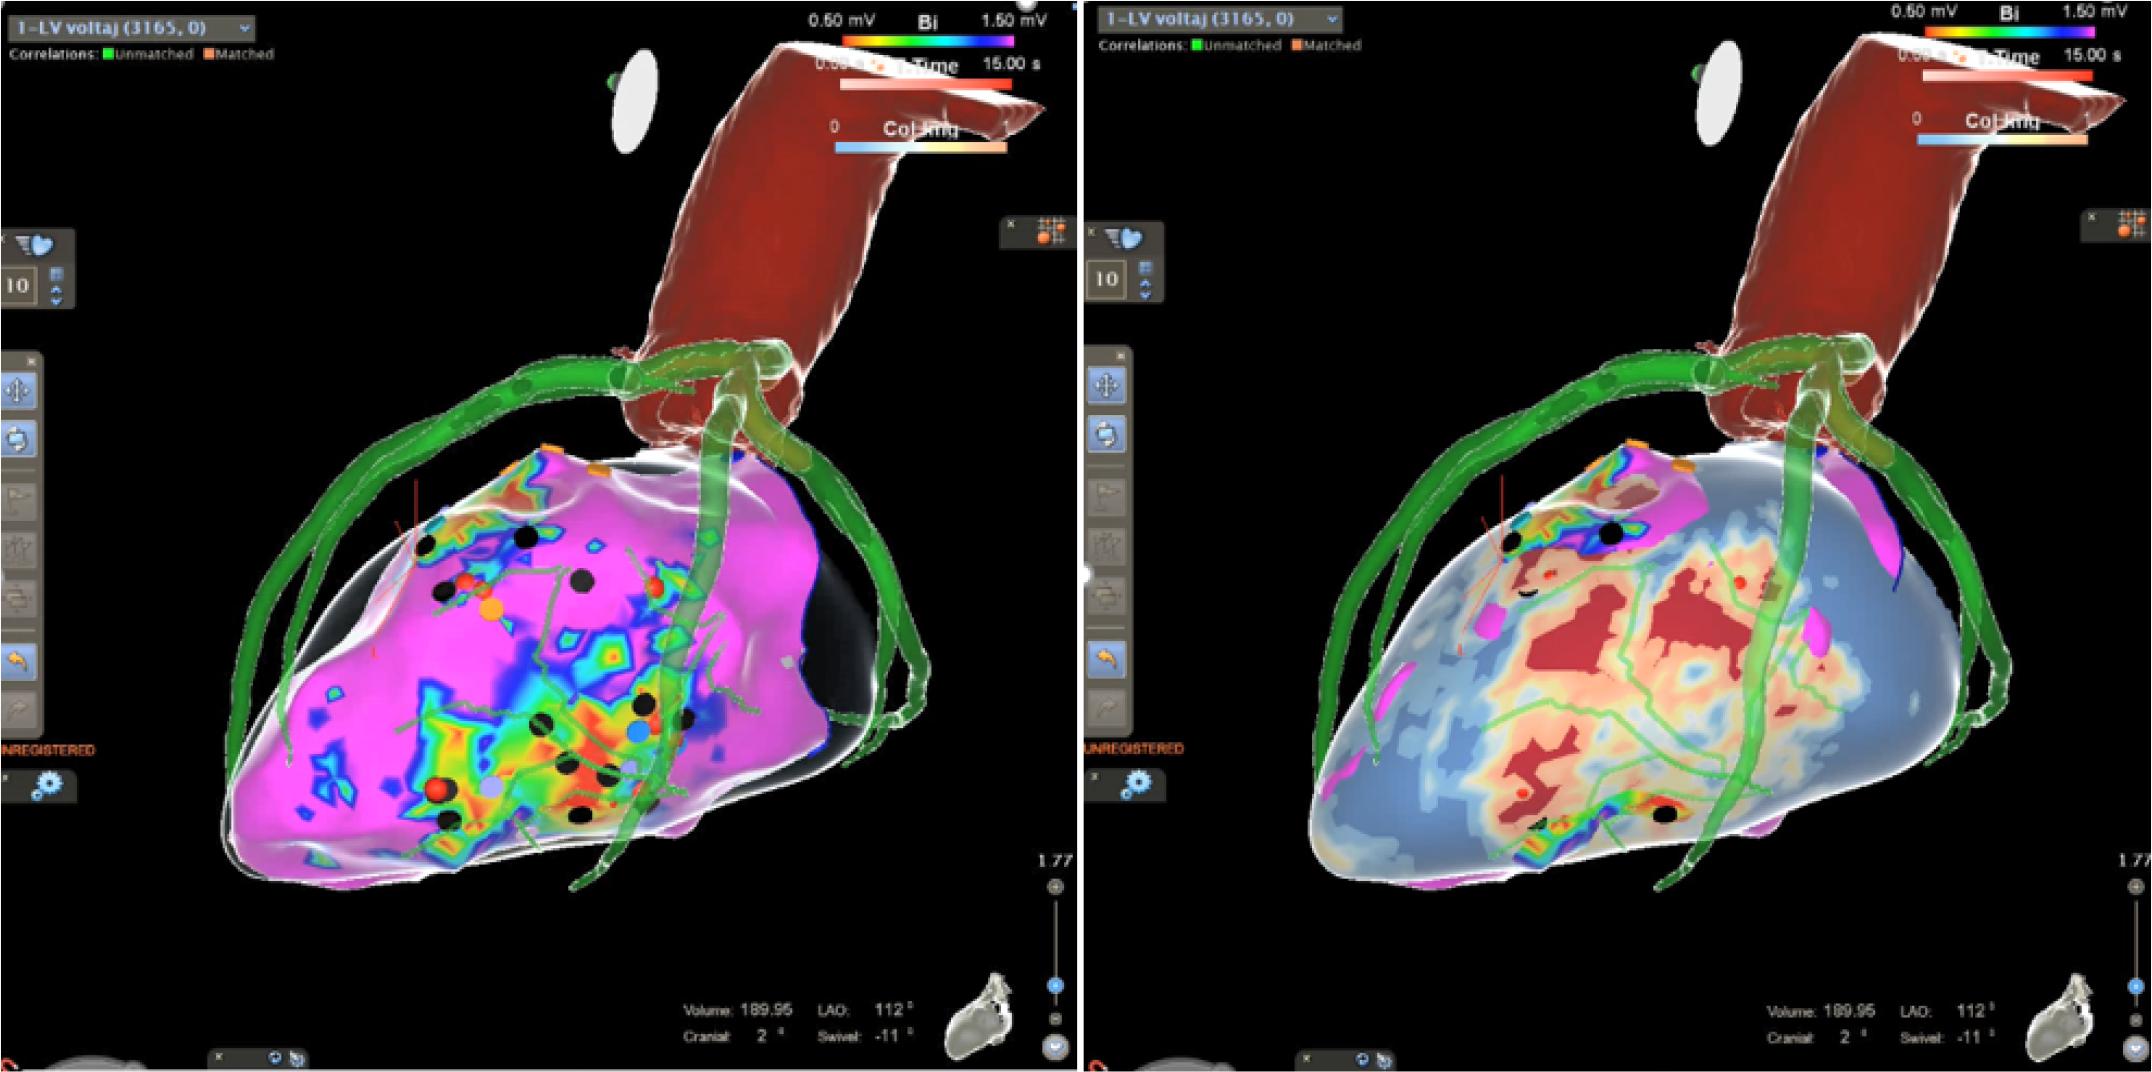

This was performed using multimodal integration of late gadolinium enhancement cardiac magnetic resonance (LGE-CMR), multi-detector computer tomography (MDCT), and electro-anatomical mapping system (EAM). Substrate imaging of scar architecture was analyzed with ADAS 3D software, revealing potential VT isthmuses.

Mapping was conducted with Carto 3 Biosense Webster and Stereotaxis Remote Magnetic Navigation System. A detailed electro-anatomical map of more than 3000 points obtained during sinus rhythm was fused with LGE-CMR/MDCT data, using coronary artery ostia as a reference point. The majority of the conduction channels were anatomically consistent between the EAM and LGE-CMR/ MDCT fusion map. (Fig. 4)

Multimodal image integration. Right: Fusion between MDCT and LGE-CMR PSI Map (ADAS 3D Software). Left: Integration with EAM (Biosense – Webster Carto 3 Navigation System)